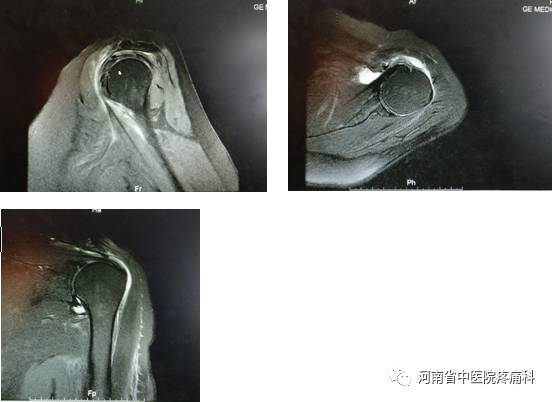

【辅助检查】血常规:(-)、肿瘤标志物(-)、类风湿、风湿(-);左肩关MRI(图示1)。

【诊断】1、左肩关节周围炎 2、左冈上肌肌腱变性